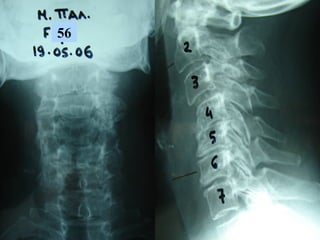

33rdrd

casecase

Ma. Pal.

F 56

Unknown origin

Symptoms

Neurologic deficit

Pain

Low fever

56

Follow upFollow up